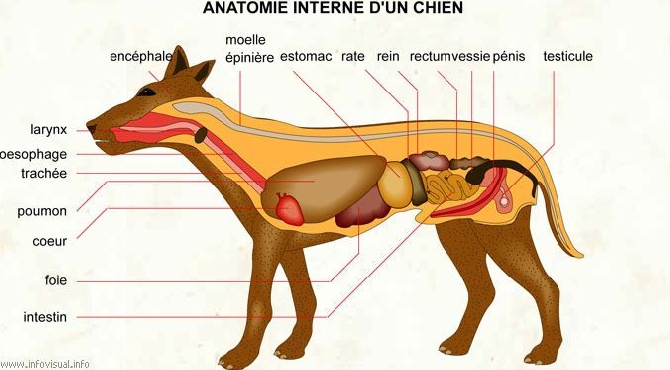

Digestion et anatomie du chien

Il existe trois types d'anatomie du système digestif chez les mammifères:

Les herbivores ont le système digestif le plus long, conçu pour...